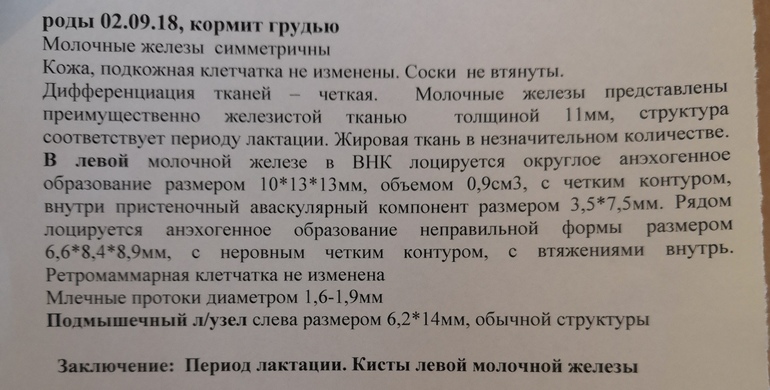

Недели 3 назад нащупала горошину в груди, гулящую, вообще не беспокоит вроде, но было пару раз ощущения побаливания, пострелывания. В общем записалась я к маммологу на 20 марта, а тем временем сделала УЗИ молочных желез. Узистка увидела 2 кисты, сказала ничего страшного, сказала проконсультироваться у маммолога.

Пугает вторая киста - непонятной, неправильной, формы с врастаниями во внутрь самой кисты - на фото видно.